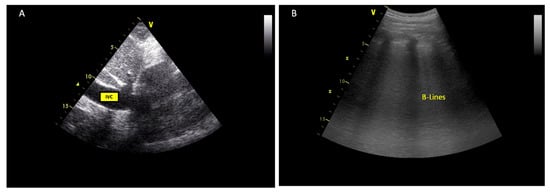

| Congestion parameters | IVC diameter | Used to estimate RA pressures | IVC < 21 mm that collapses > 50% |

| VExUS Score | |

| Grade 0 | IVC < 20 mm |

| Grade 1 | IVC ≥ 21 mm |

| Normal patterns or mild findings | |

| Grade 2 | IVC ≥ 21 mm |

| Severe finding in only one organ | |

| Grade 3 | IVC ≥ 21 mm |

| Severe findings in multiple organs | |